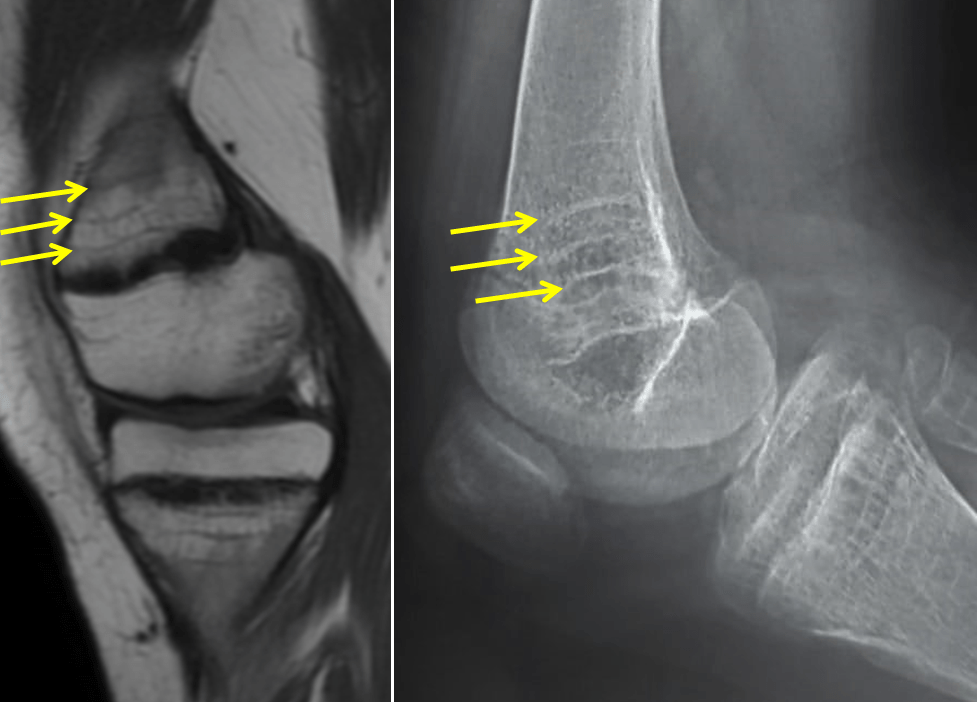

The Harris growth arrest line is an increased bone density representing

Growth arrest lines Radiology Case Arrested Growth Meaning The act of ceasing to grow. Learn how to cope, heal, and recover from arrested development. Arrested development is a condition where an individual’s growth and maturation are hindered during childhood. Examples of arrested development in a sentence, how to use it. Examples of 'growth arrest' in a. Arrested development in human hookworm infections : When trauma impairs your ability. Arrested Growth Meaning.

From radiopaedia.org

Growth arrest lines and physeal stress injury Image Arrested Growth Meaning The act of ceasing to grow. Examples of arrested development in a sentence, how to use it. When trauma impairs your ability to develop full emotional maturity, this is known as arrested psychological development. Arrested development, in the realm of psychology, refers to an abnormal cessation or delay in the physical or emotional growth of an individual,. Arrested development is. Arrested Growth Meaning.

From www.wikiradiography.net

Harris Growth Arrest Lines wikiRadiography Arrested Growth Meaning Examples of arrested development in a sentence, how to use it. Arrested development is a condition where an individual’s growth and maturation are hindered during childhood. Arrested development, in the realm of psychology, refers to an abnormal cessation or delay in the physical or emotional growth of an individual,. Arrested development is a term used in medicine and psychology to. Arrested Growth Meaning.